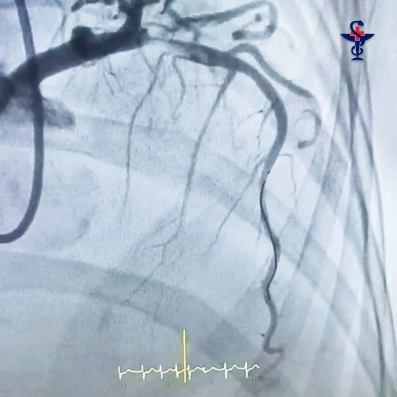

Приняв решение о проведении коронарографии и установки стента, врачи экстренно отправили больную в рентгеноперационную.

При контрастном исследовании проходимости сосудов сердца врачи обнаружили огромный тромб. Он практически полностью перекрыл просвет сосуда, что могло вызвать поражение сердца (инфаркт). В таком случае процент летального исхода возрастает в разы.

«По меркам сосудов сердца – это очень крупный и протяженный тромб, который мы успешно удалили, установили специальный стент (металлический каркас) и полностью восстановили проходимость коронарной артерии», – прокомментировала ход операции врач по рентгенэндоваскулярной диагностике и лечению Аделя Творогова.